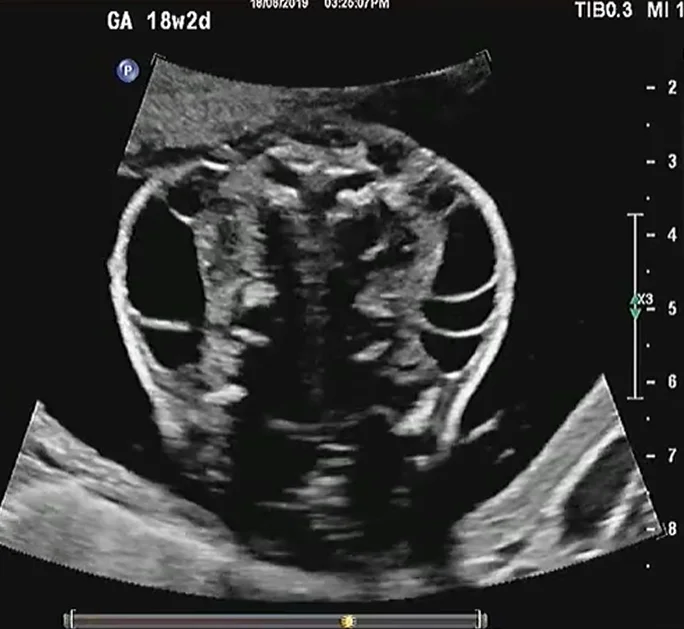

• U quái vùng cổ thai nhi (Cervical Teratoma)